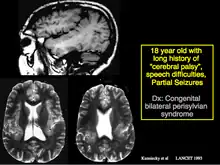

He was one of the first to recognize and prove that mesial temporal sclerosis, a common cause for difficulty in controlling temporal lobe epilepsy, can be identified with MRI scans. He also described the Kuzniecky Syndrome in 1991, also known as perisylvian polymicrogyria. The syndrome is characterized by seizures, cognitive abnormalities, and a peculiar inability to use the mouth and tongue muscles. This syndrome is recognized by as a specific malformation of the brain.

Kuzniecky described the Kuzniecky Syndrome in 1991, also known as perisylvian polymicrogyria.[6] The syndrome is characterized by seizures, cognitive abnormalities, and a peculiar inability to use the mouth and tongue muscles. This syndrome is recognized by as a specific malformation of the brain.[7]